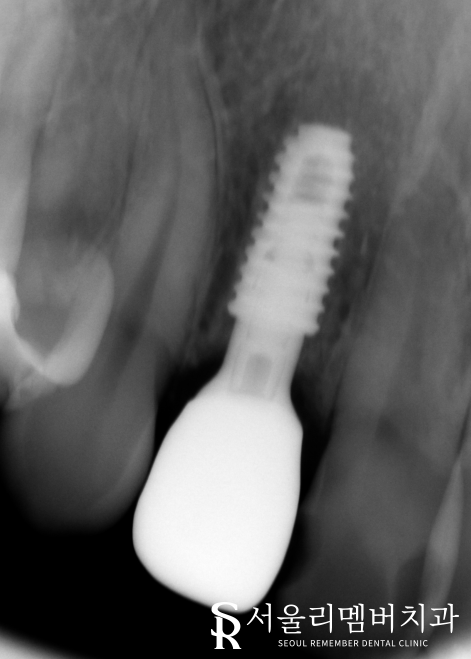

남아있는 조직을 깨끗하게 제거한 뒤, 본격적인 식립 과정에 들어갔습니다.

다행히 치조골 손상은 심하지 않았기 때문에 바로 심을 수 있을 것 같네요.

주변 조직과의 거리, 인접치와의 위치 관계를 따져 미리 계산된 위치에 픽스쳐를 심어드렸습니다.

골융합 정도를 확인한 뒤에 보철을 올려드리기로 했는데요.

몇달이 지나고 단단하게 결합된 픽스쳐를 확인할 수 있었습니다.

이젠 최종 보철을 올려도 되겠네요^^

파노라마 상에서도 볼 수 있듯이

매끄럽게 제작 된 보철이 관찰되네요.